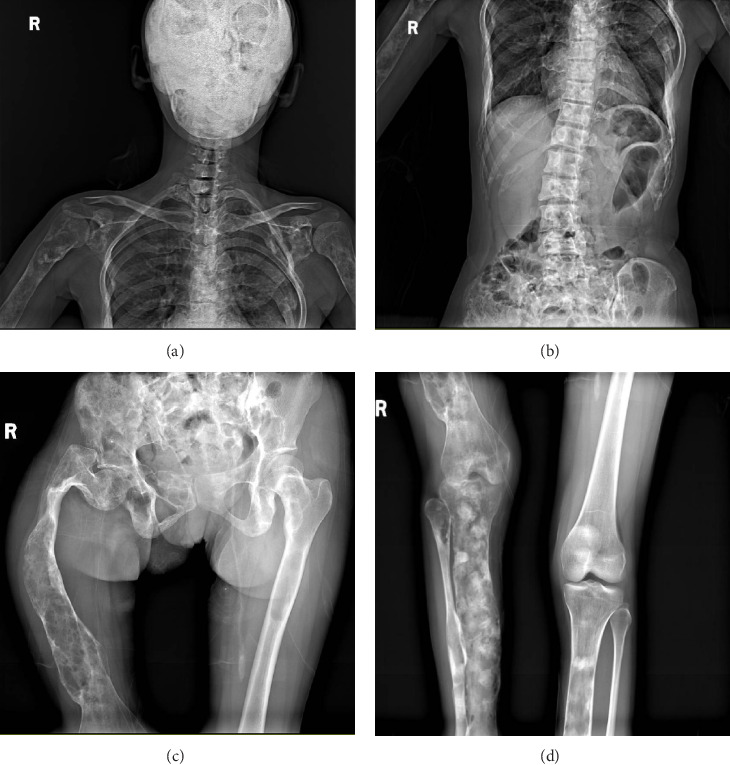

Background: Fibrous dysplasia (FD) is a rare congenital bone disease. Denosumab, a monoclonal antibody targeting nuclear factor kappa-B ligand (RANKL), suppresses osteoclast activity and exhibits therapeutic potential for FD. Case Presentation: We present the case of an adult female patient diagnosed with FD who had undergone 7 treatment cycles of denosumab (120 mg/dose, sc.) with a cumulative dose of 840 mg. After discontinuing denosumab for 7 months, the patient experienced a crisis of rebound hypercalcemia. Conclusion: Although, rare reports of hypercalcemia induced by discontinuation of denosumab are primarily seen in adolescents. By reporting this case, we aim to alert clinicians to the risk of rebound hypercalcemia in adult patients with FD undergoing denosumab treatment.